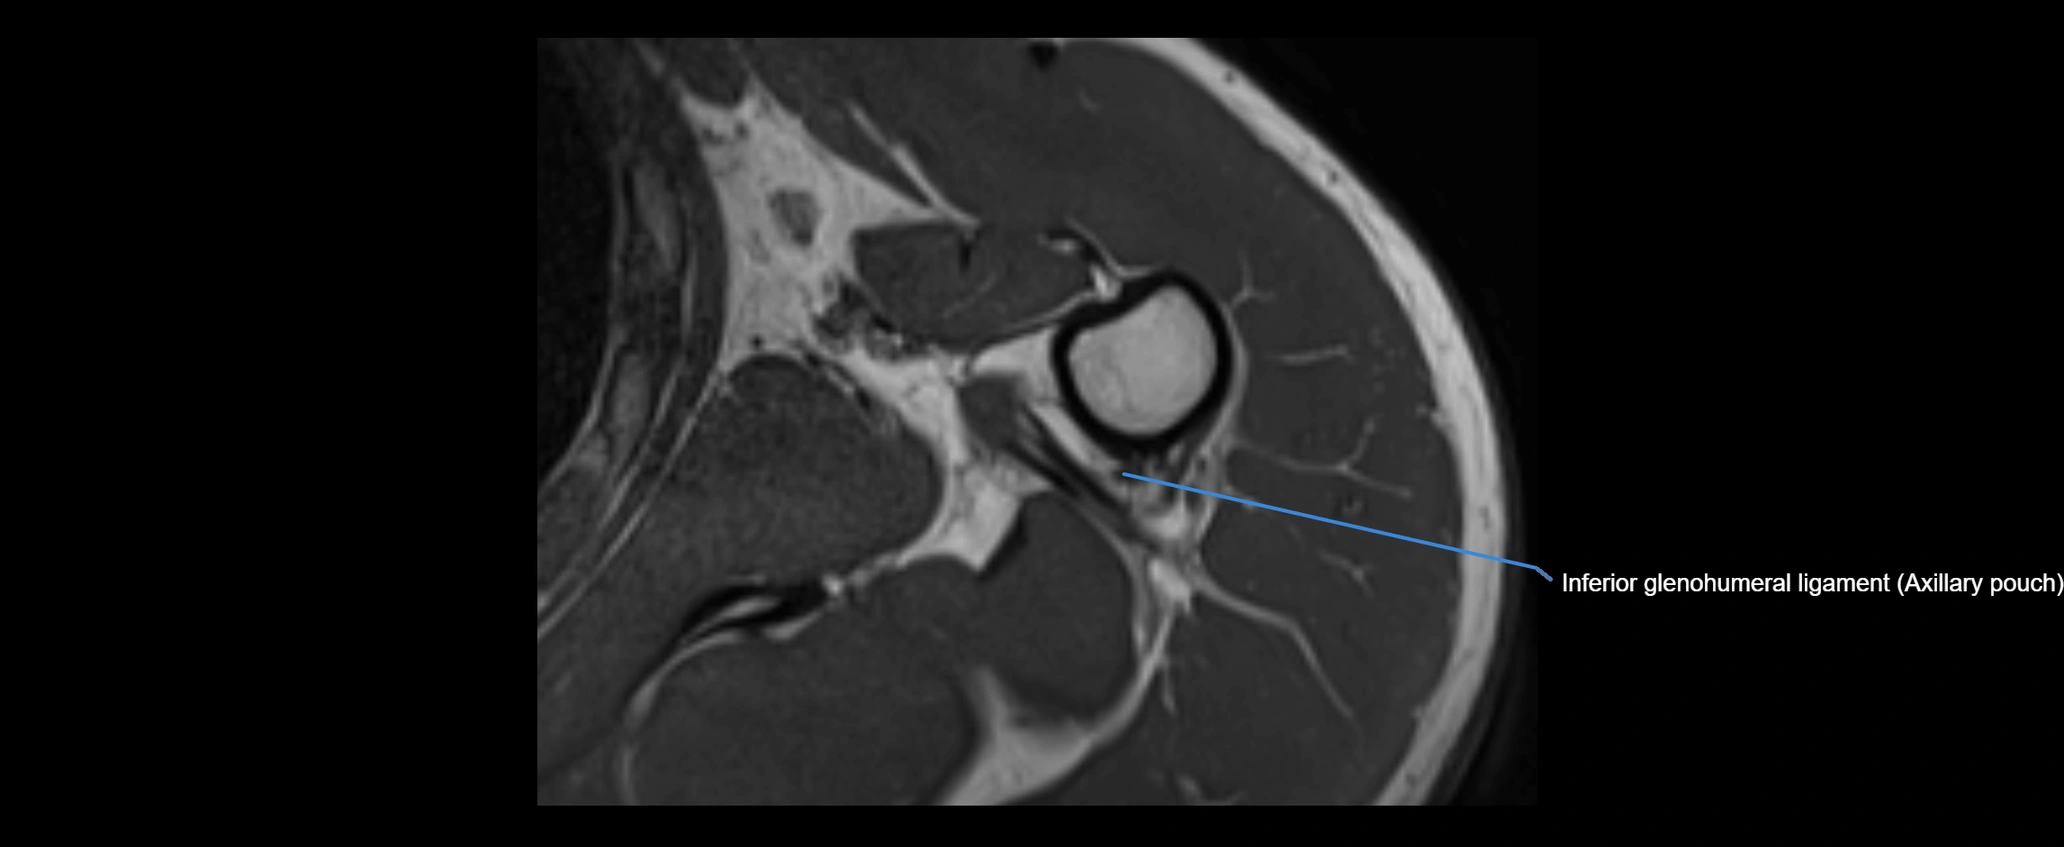

MRI images

image